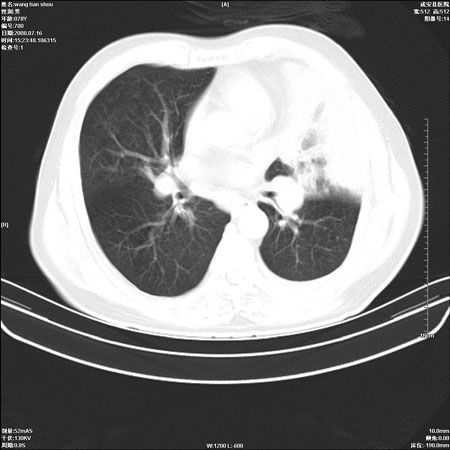

以下是引用qingjing在2008-7-16 19:55:00的发言:[br]1、左上肺不张并堵塞性炎症,建议支气管镜详查;[br]2、左侧胸腔少量积液。

以下是引用wzr在2008-7-16 20:26:00的发言:[br]左肺肺不张伴阻塞性肺炎!另:左侧胸腔少量积液。建议纤支镜检查!